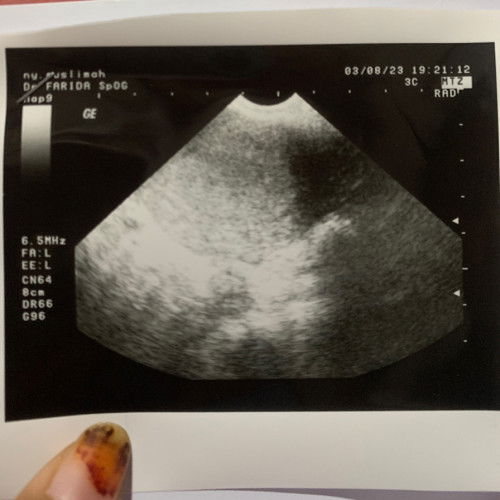

Halo moms . Hpht ku tgl 26juni dan tgl 31juli kemaren aku tastpack garis dua jelas . Kalau di aplikasi udah masuk 5minggu . Dan aku usg perut dan usg transvagina tapi belum terlihat kantung janin seperti gambar . Kata dokter usg lagi 2mingguan . Apakah normal kalau blm terlihat kntung janin? Tapi aku sudah merasakah hamil sprti mual muntah . Mohon Pencerahannya moms #ingintahu #firstmom #firstbaby